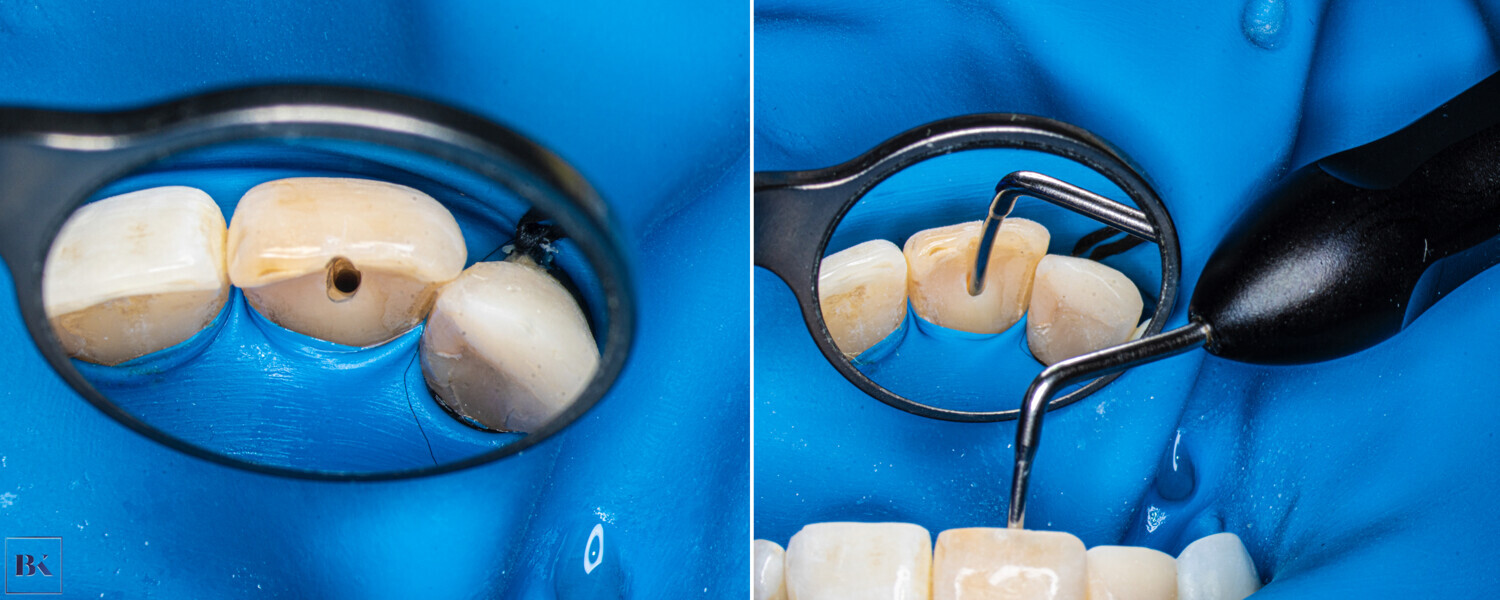

A 36-year-old female patient came to the dental office with discoloration and pain of the maxillary right first incisor (Fig. 1). In the medical history taking, she reported a trauma approximately 15 years earlier. During the radiographic examination in the office of her general dentist, PCO was revealed. She was referred for a CBCT scan and endodontic treatment.

During the consultation, the CBCT scan was performed with the 9000 C 3D with a voxel size of 0.1 mm (Carestream). The CBCT scan revealed a highly calcified pulp chamber and an almost invisible trace of the root canal (Fig. 2). The patient was informed about the new, beneficial technology which can help to preserve additional tooth structure during treatment.

Fig. 1: Intra-oral view of the initial situation. Visible discoloration of the right central incisor.

Figs. 2a & b: CBCT scan, sagittal (a) and coronal planes (b). Visible pulp canal obliteration and periapical lesion.